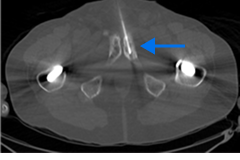

High-risk patient with newly diagnosed prostate cancer

Age

72

PSA (ng/mL)

5.1

Gleason Score

4 + 4

PYLARIFY prompted treatment change from prostatectomy to systemic therapy, thereby avoiding undertreatment